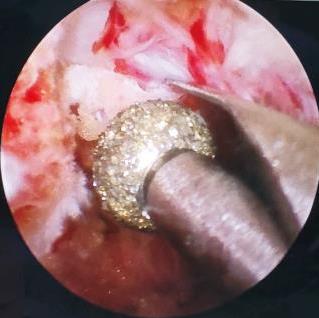

• 关节镜下前交叉韧带重建术后对侧韧带损伤的风险预警可视化模型的研究及其应用价值

摘要:目的 构建关节镜下前交叉韧带(ACL)重建术后对侧韧带损伤的风险预警可视化模型,并对预警模型行内部验证,以期为医护人员评估ACL损伤患者术后对侧韧带损伤风险提供简洁、直观和高效的个体化评估工具。方法 选取2021年1月-2024年1月该院所有行关节镜下ACL重建术治疗的ACL损伤患者583例,排除失访和资料不完整的51例患者后,最终纳入532例患者。根据是否发生关节镜下ACL重建术后对侧韧带损伤,将患者分为发生组(n = 42)与未发生组(n = 490),采用单因素分析比较两组患者临床资料,采用R软件,通过多因素二分类Logistic回归分析,获取预测因子和回归系数,建立可视化列线图预警模型,并采用校准曲线、C指数和决策曲线,进行一致性、区分度和临床适用性等内部验证和外部验证。结果 多因素Logistic回归分析显示,运动员、女性、膝关节内扣、术后6周Lachman试验阳性、术后3个月国际膝关节文献委员会(IKDC)评分、年龄 < 20岁和术前胫骨平台后倾角(PTS)是关节镜下ACL重建术后对侧韧带损伤的影响因素(P < 0.05);在此基础上,应用R软件建立可视化列线图预警模型,经Bootstrap检验后显示,C指数为0.892;绘制受试者操作特征曲线(ROC curve),该模型在内部验证集和外部验证集中的曲线下面积(AUC)分别为:0.820(95%CI:0.751~0.890)和0.799(95%CI:0.712~0.886);绘制校准曲线,该模型内部验证集和外部验证集中的斜率均近似为1;决策曲线中,该模型内部验证集和外部验证集均具有明显净获益。结论 关节镜下ACL重建术后,对侧韧带损伤受年龄、性别、术后6周Lachman试验阳性、膝关节内扣、术后3个月IKDC评分、术前PTS和运动员的影响,据此构建的可视化预警模型,具有良好的临床应用价值,可指导临床工作者开展针对性干预。